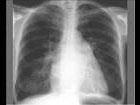

问题 女,21岁,反复关节红肿疼痛5年,活动后心悸气促1天入院。查:梨形心界,心率88次/分,律齐,心尖区舒张期隆隆样杂音,P亢进;Hb88g/L;胸片结果如图所示。可诊断为 ( )

选项 A、冠心病 B、Austin-Flint杂音 C、贫血 D、风心病、二尖瓣狭窄 E、左房粘液瘤

答案 D